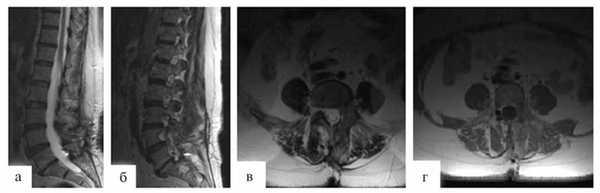

В послеоперационном периоде через 3 мес после операции пациентке выполнена МРТ, по результатам которой подтверждено радикальное удаление опухоли (рис. 3).

Рисунок 3. Контрольное МРТ-исследование через 3 мес после операции. а - Т2 режим, сагиттальная проекция; б, в - Т1 режим с контрастным усилением: б - сагиттальная проекция, в - аксимальная проекция.